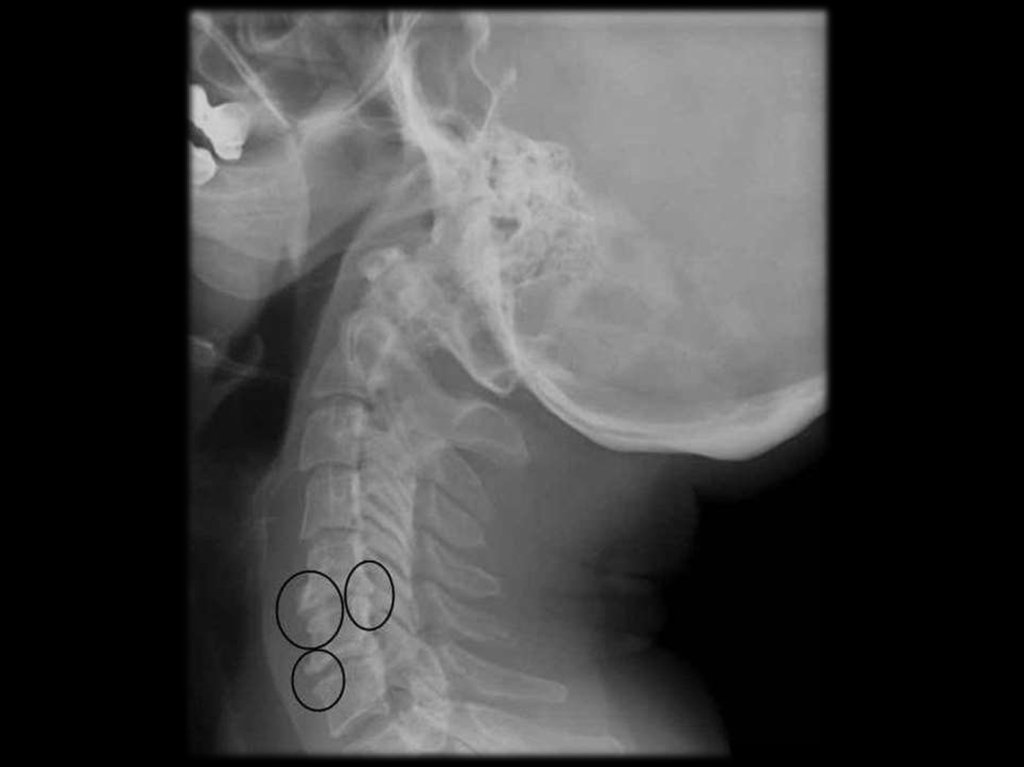

В шейном отделе клинически наиболее значимы

остеофиты

и

артрозы

унковертебральных

сочленений.

остеофиты и артрозы унковертебральных сочленений.